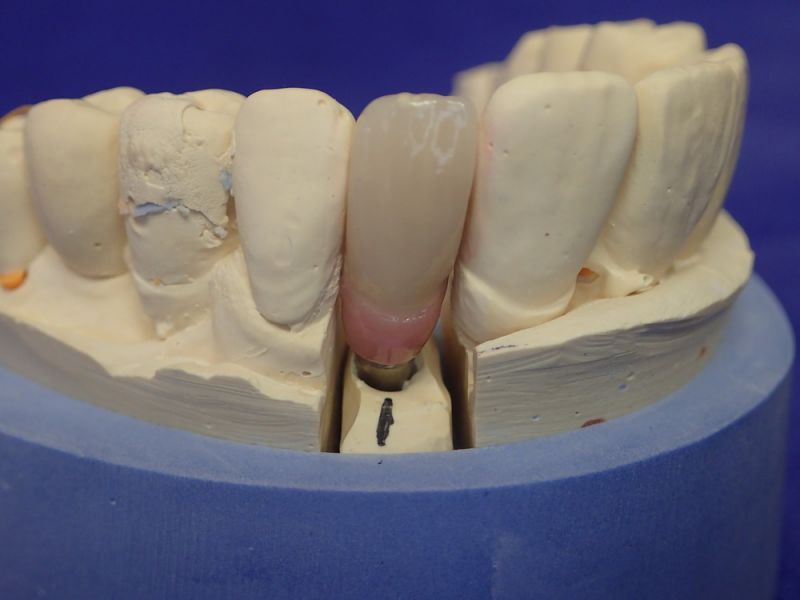

Kieler Patient erhält implantatgestützte Kronenversorgung 22

In diesem Fall wäre es sogar möglich gewesen auf das neue Implantat 22 zu verzichten und eine Versorgung auf den vorhandenen Implantaten zu begründen.

Das hätte aber zu einem wesentlich höheren wirtschaftlichen Aufwand geführt, weil die dann notwendige Prothetik, die von den Implantaten hätte entfernt und nachfolgend wieder neu hätte erstellt werden müssen, wesentlich teurer gekommen wäre, als ein neues Implantat mit einer neuen Krone darauf.